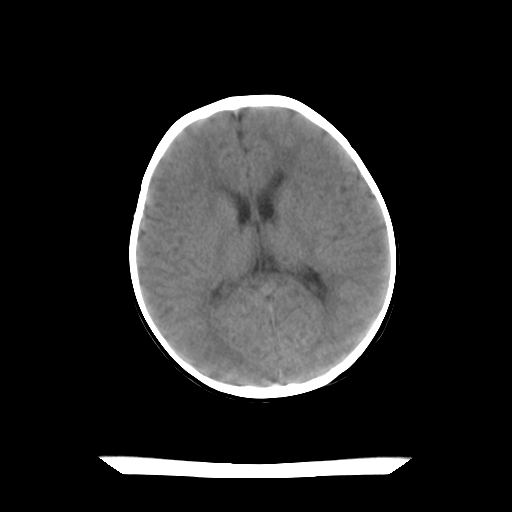

女,10个月,头外伤三天,伤后爱哭闹,吃奶少,睡觉不踏实。

1)左侧颞极蛛网膜囊肿。2)第四脑室出血?

1)左侧颞极蛛网膜囊肿。2)不排除第四脑室出血!

左侧颞极蛛网膜囊肿,第四脑室出血?